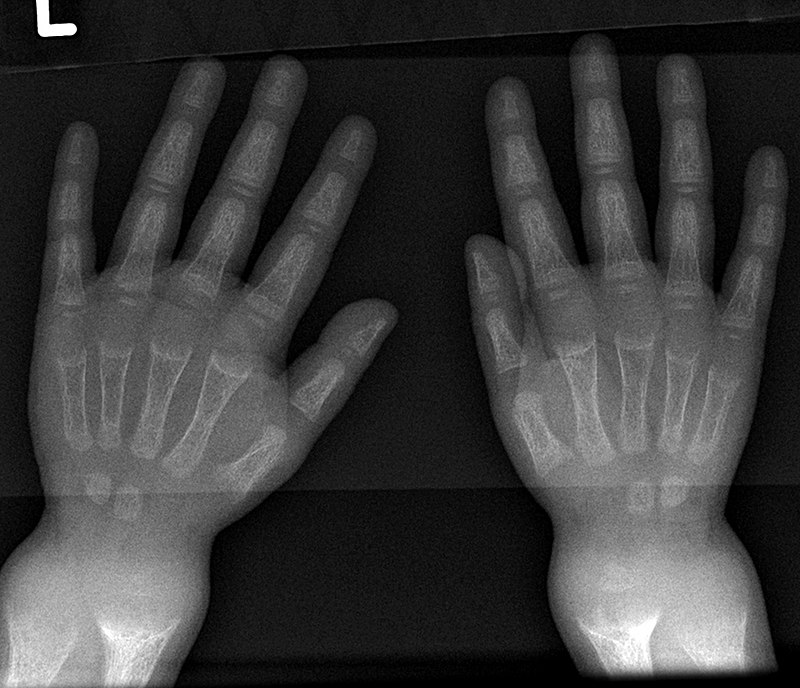

Chondroma

Chondromas are benign tumors composed of cartilage.

Chondromas typically develops in the medulla of the small bones in the hands and feet.